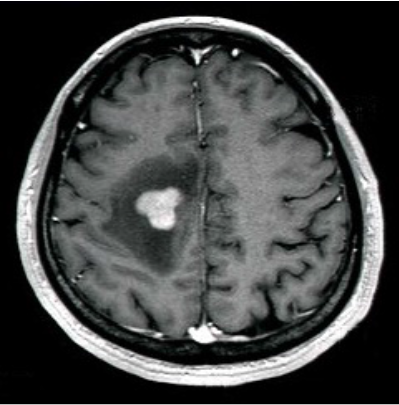

画像診断

脳の造影剤を用いたMRI検査で特徴的な所見が認められることがありますが、どんな形にもなりうる腫瘍としても有名です。(左図)